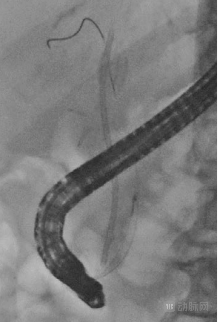

常规条件

应用Accent后

图片所示患者,因碎石后胆结石残留而植入塑料支架,支架误入胆道,需要使用取石网篮对支架和残留结石进行回收。应用Accent后,支架下端的开口和取石网篮的导线、导丝均清晰可见,医生顺利完成了支架回收手术。